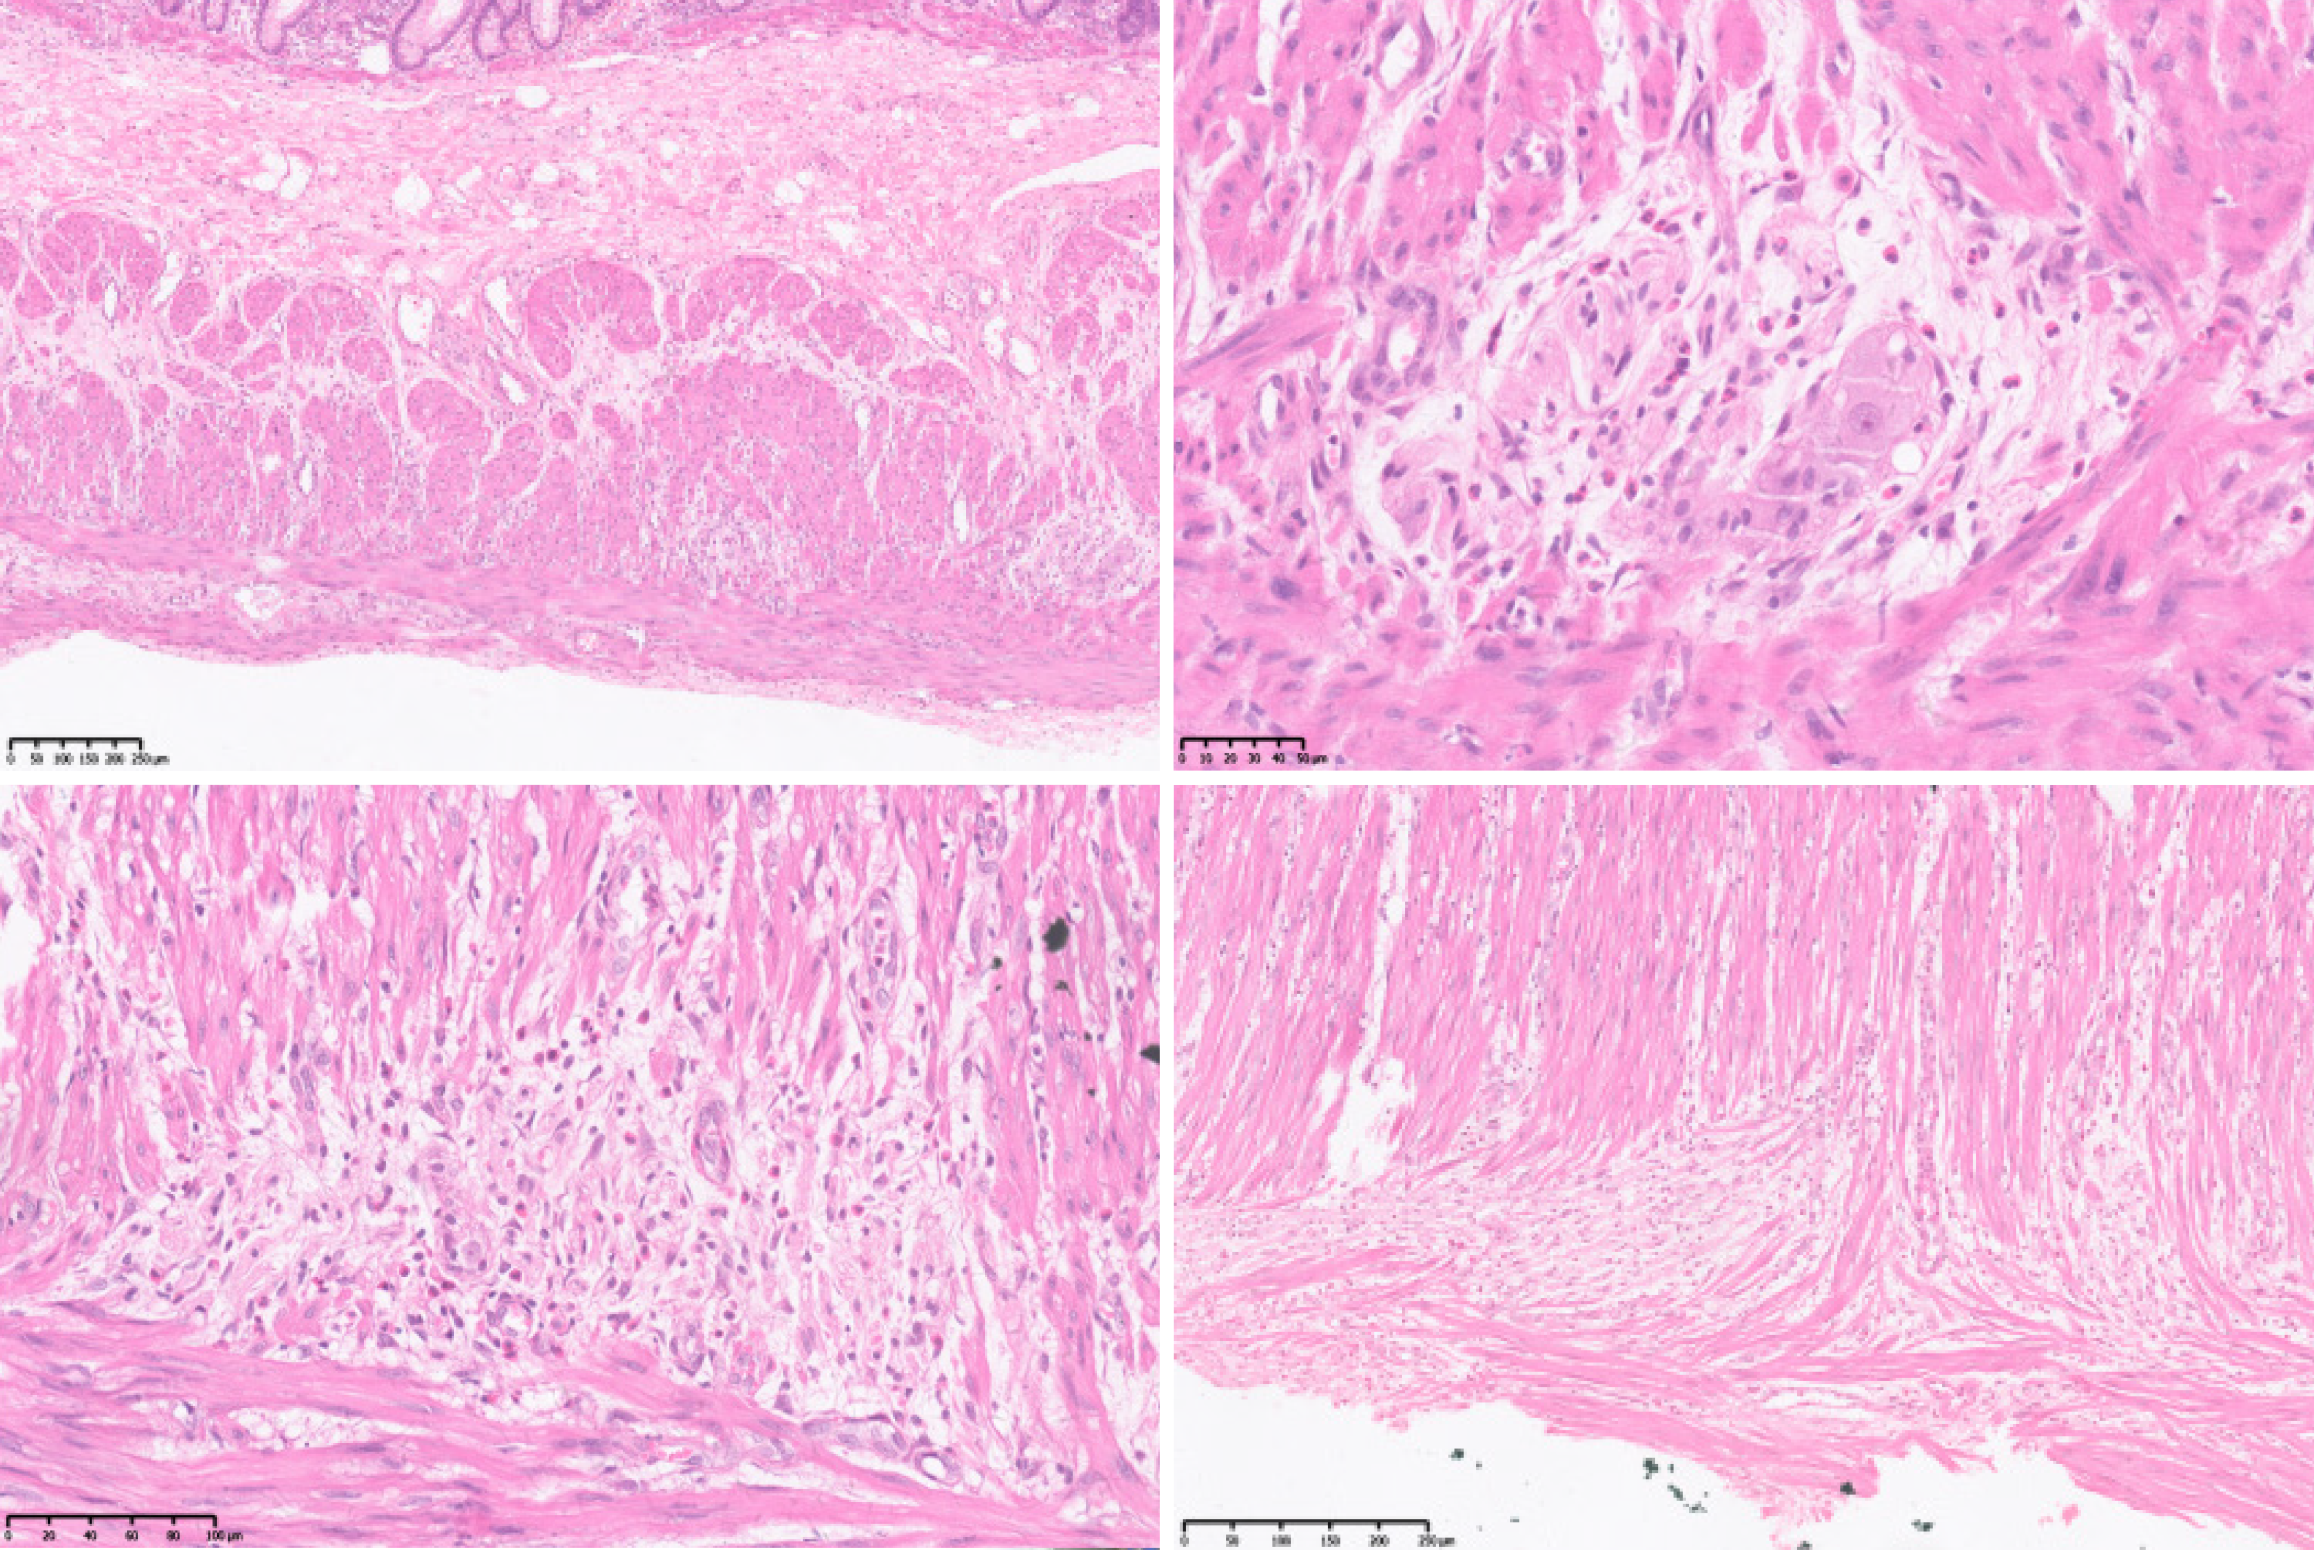

Nerve conduction studies showed that peripheral neuropathy predominantly affected sensory fibers in both lower limbs. A pathological specimen of the resected intestinal segment obtained in 2008 was submitted to the pathology department of our hospital for consultation. The examination revealed muscle fiber atrophy in the muscular layer of the colon, no significant reduction in ganglion cell number, nerve fiber proliferation and disorganization, partial ganglion cell degeneration, or eosinophilic infiltration (Figure 4).